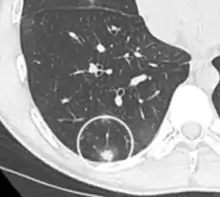

CT image showing ground-glass nodule (circled).